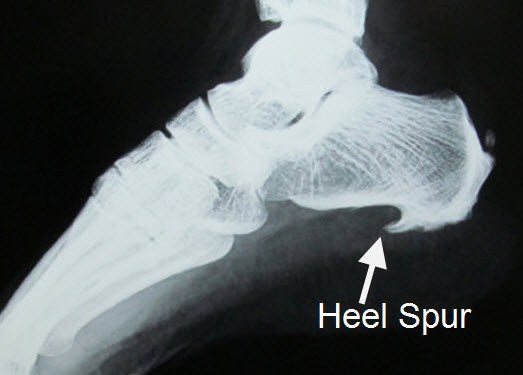

이런 상태에서 제대로 치료받지 못하고 만성으로 넘어가면

근막 내부에 석회가 끼기도 하고 뼈가 자라나기도 합니다.

뼈가 자라난다고 전부 족저근막염인건 아니고

류마티스 관절염과 척추관절병증에서도 나타나니까 이런 면역계 질환이 아닌지 추가적인 검사가 필요합니다.